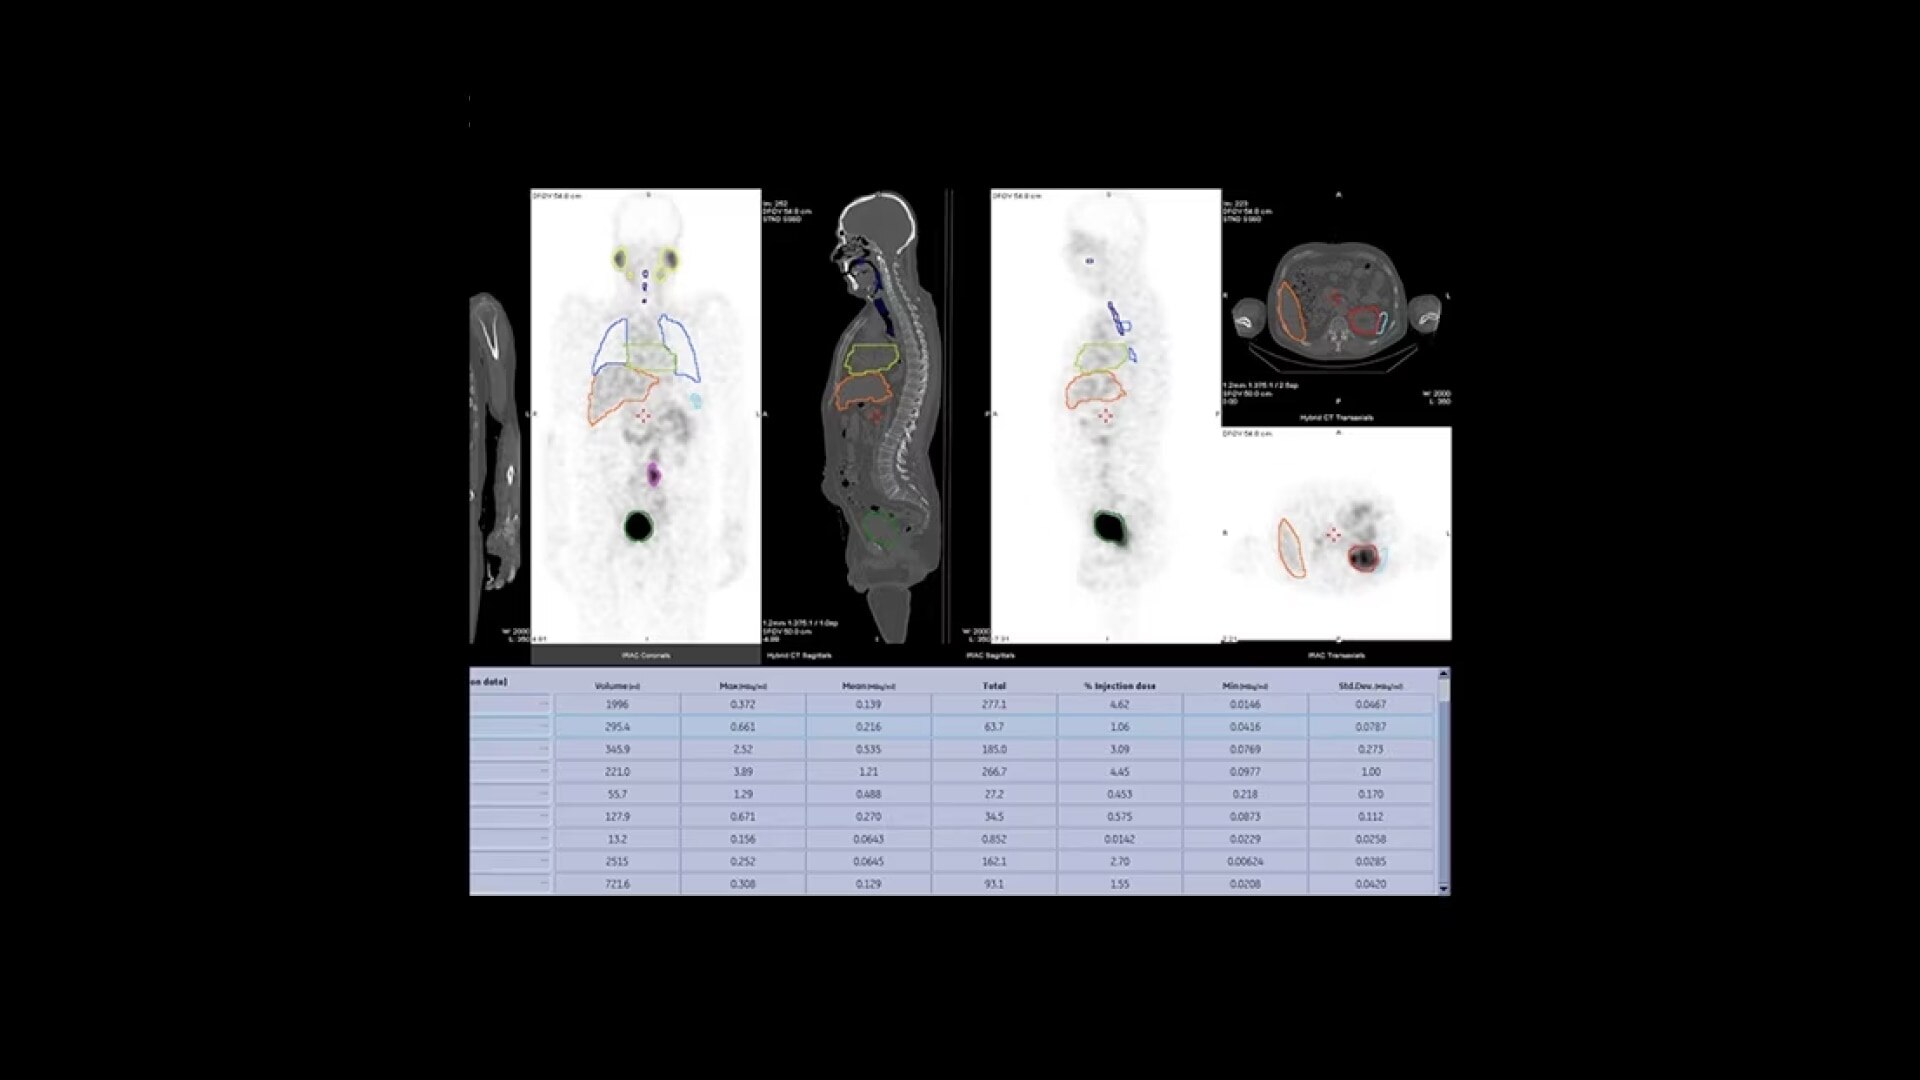

Quantitative SPECT/CT for every patient, every day

NM/CT 870 DR is a SPECT/CT built for consistent, reproducible quantitation. Improvements to detector performance enable exceptional spatial resolution for SPECT and planar images. It leverages CT-based attenuation and scatter correction along with Evolution⁴ image reconstruction. Ever-increasing computational power enables precise camera calibration for less variation between exams.

Once your quantitative studies are acquired, SmartConsole with Xeleris, makes it easier to access them - your quantitative SPECT/CT studies are automatically transferred directly to the PACS or other pre-defined DICOM destinations. An additional dataset in PET DICOM format allows you to review and evaluate images on the same devices you use to view your PET/CT studies, as adjacent information to the original SPECT/CT images.